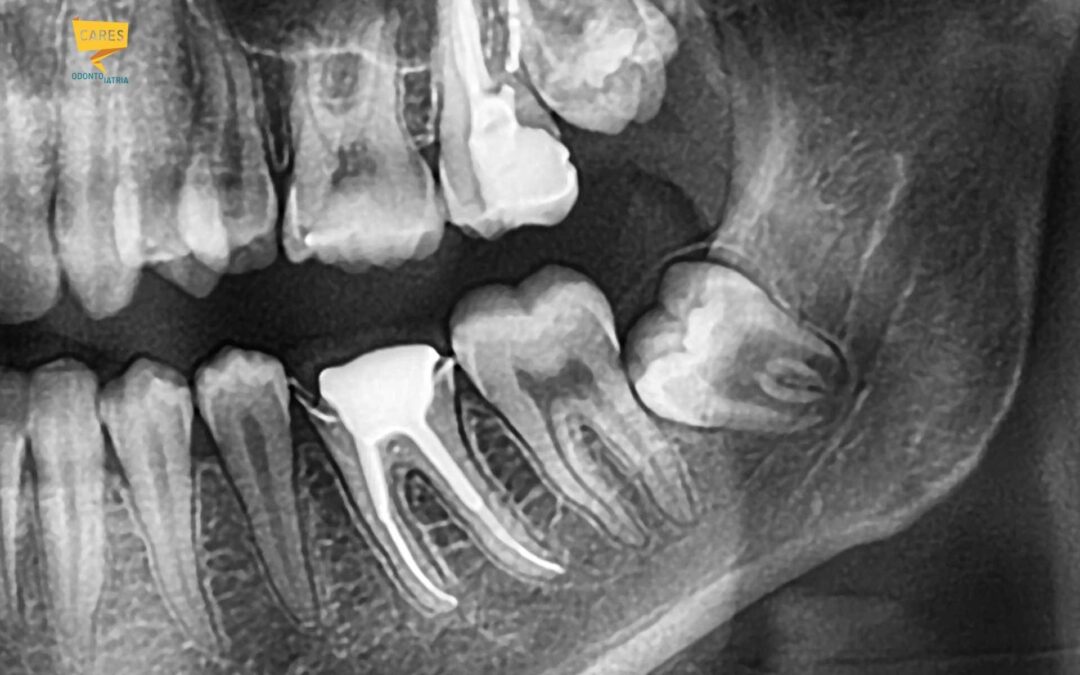

Carie dentali: rla presenza di carie che hanno indebolito e privato il dente di parte dello smalto dentale di protezione sono spesso la causa di una forte sensibilità sia al caldo che al freddo, ma possono anche dare una sensazione di dolore con i cibi dolci e zuccherini. Questo per via della esposizione della parte interna del dente, la dentina che è in diretta comunicazione con la polpa dentale che racchiude il nervo.

Oltre alle carie, esiste un altro meccanismo che lentamente ed inesorabilmente priva i nostri denti dello smalto protettivo ed espone la parte sottostante, la “dentina”, alle intemperie della bocca, ed a tutti i cibi e bevande che introduciamo, rendendo il dente estremamente sensibile.

Colletti dentali scoperti, avere i colletti dentali scoperti è la principale causa di ipersensibilità dentale, le cause di questa perdita di protezione possono essere traumatiche, come ad esempio disturbi dell’occlusione per denti storti o bruxismo o dovute ad abrasione per manovre di pulizia sbagliate con utensili di vario genere o allo spazzolamento errato e troppo energico con spazzolini dalle setole troppo dure, oppure dall’utilizzo di bicarbonato o acidi vari -come il limone- che non vanno mai utilizzati per lavare i denti!

Recessione gengivale, ossia il ritiro delle gengive, frequente nelle zone estetiche come i premolari, i canini, ma anche sugli incisivi, che oltre a rovinare l’armonia del sorriso consentono l’esposizione di parti del dente normalmente protette dalla gengiva come la dentina e la radice dentale.